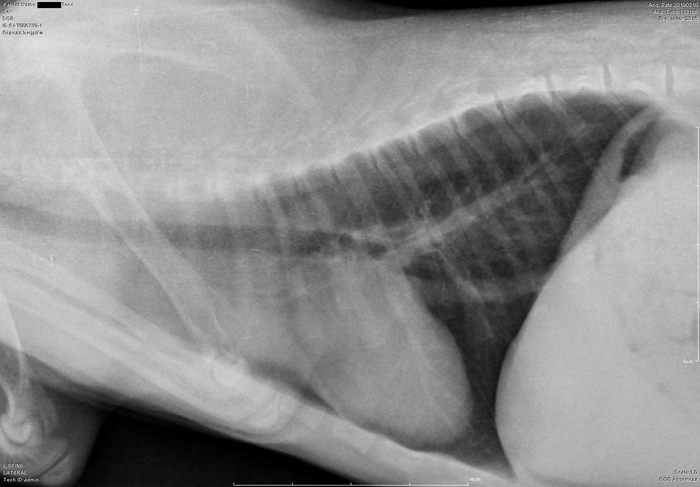

Рентген котенка

Добрый день. Котенок рожден 5 ноября 2018 года, девочка, не привита. Проглистована. Неожиданно в один момент стала припадать на задние ноги. Как бы бережет их и старается не прыгать лишний раз. Свозили два дня назад к ветеринару - всю её прощупал, говорит переломов нет, вывихов тоже. Сделали блокаду ближе в крестцу новокаина, чтобы снять симптомы. Прописал кальций в таблетках Ексел. Сейчас всё примерно так же - лапки задние бережет, но стала по активнее. Прошу специалистов, если такие тут бывают, оценить снимки, т.к. врач ещё кое-что сказал и хотелось бы услышать ваше мнение. Скан расшифровки и д/з потом приложу.

Боковая проекция